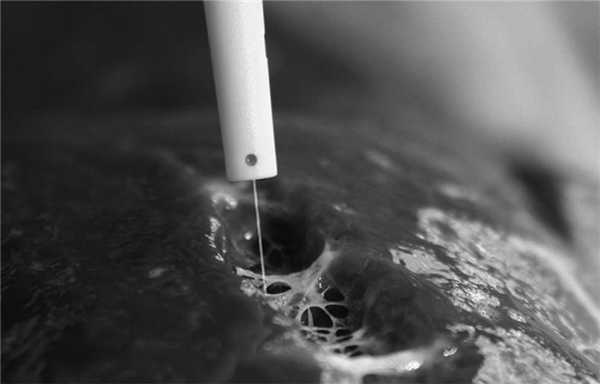

Усовершенствование методики разделения паренхимы печени позволяет добиться лучшей визуализации интрапаренхиматозных трубчатых структур и уменьшения объема интраоперационной кровопотери, снижения частоты послеоперационных осложнений. Для достижения данной цели разработано множество методов, основанных на различных физических принципах, начиная с дигитоклазии и методики «crush clamp» («раздавливания зажимом») и заканчивая радиочастотной термоабляцией, аргоновой коагуляцией, ультразвуковой и водоструйной диссекцией [12].

После развития демаркации, диссекция паренхимы печени производится в пределах ишемизированной зоны (5—10 мм от линии демаркации). На этом этапе мы параллельно используем водоструйный диссектор, гармонический скальпель, моно- и биполярную коагуляцию, а также клипирование и лигирование трубчатых структур. При этом применение водоструйного диссектора в абсолютном большинстве случаев позволяет разделить паренхиму печени без нарушения целостности мелких глиссоновых пучков, ветвей печеночных вен и желчных протоков (рисунок). Рисунок 1. Разделение паренхимы печени с использованием водоструйного диссектора.